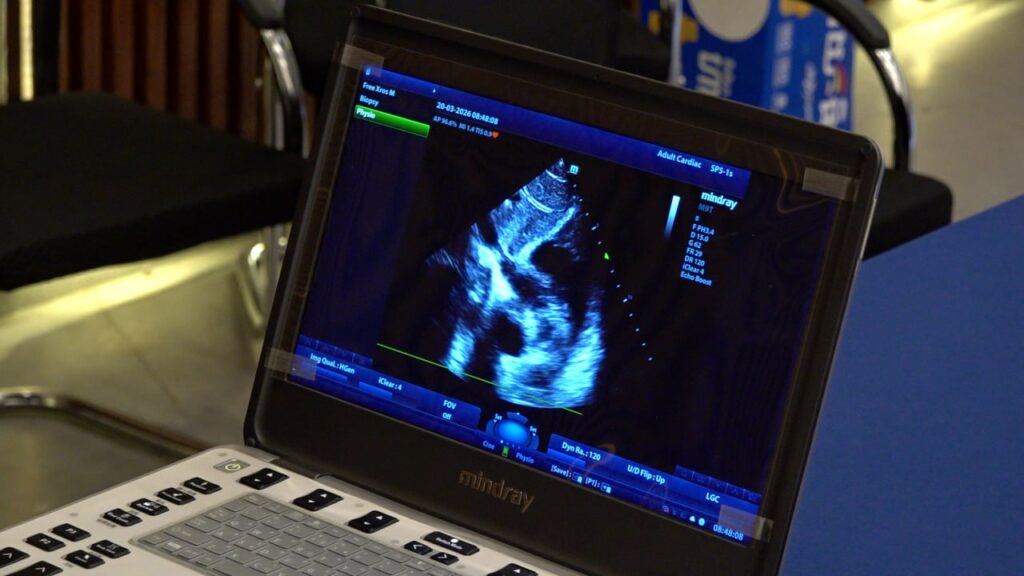

(ភ្នំពេញ)៖ ក្រុមគ្រូពេទ្យស្មគ្រចិត្តកម្ពុជា-ចិននៅព្រឹកថ្ងៃទី២០ ខែមីនា ឆ្នាំ២០២៦ បានរៀបចំកម្មវិធីមនុស្សធម៌ចុះពិនិត្យសុខភាពបេះដូងដោយឥតគិតថ្លៃ ជូនដល់សិស្សានុសិស្សចំនួន ៧៣០នាក់ នៅសាលាមធ្យមសិក្សាវិចិត្រសិល្បៈ ។ សកម្មភាពនេះរួមមាន ការត្រួតពិនិត្យសម្ពាធឈាម ការស្កេនបេះដូង និងការផ្តល់ប្រឹក្សាផ្នែកអាហារូបត្ថម្ភ។

សំឡេង៖ «ពេលនេះ ក្រុមគ្រូពេទ្យខ្មែរ-ចិន យើងមកគឺមាន ទី១ គឺមានវេជ្ជបណ្ឌិតឯកទេស។ វេជ្ជបណ្ឌិតឯកទេស ដែលគាត់មានជំនាញច្បាស់លាស់ ក្នុងការធ្វើរោគវិនិច្ឆ័យ ជំងឺបេះដូងពីកំណើត ទី១។ ទី២ យើងភ្ជាប់ជាមួយឧបករណ៍ផ្សេងៗទៀត ដូចជា ស្ដេតូស្កុប (Stethoscope) ដើម្បីយើងស្គ្រីននីង (Screening) ហើយក៏យើងមាន អេកូកាដ្យូក្រាហ្វី (Echocardiography) ណា អេកូបេះដូង ដើម្បីធ្វើរោគវិនិច្ឆ័យ ឱ្យបានច្បាស់លាស់ ។»